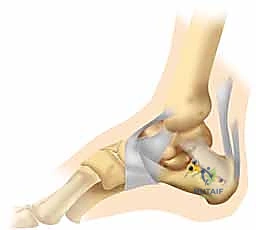

3. كشف الكسر وإعادة البناء (Reduction)

بمجرد كشف العظم، يتم تنظيف التجمع الدموي. يقوم الجراح بكشف السطح المفصلي المكسور. باستخدام أدوات دقيقة، يتم رفع الشظايا العظمية المنخسفة إلى مكانها التشريحي الأصلي. يتم استعادة ارتفاع وعرض العظم، والأهم من ذلك، استعادة السلاسة التامة لسطح المفصل.